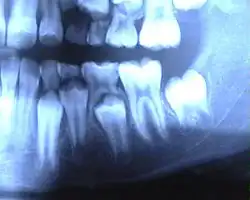

![]() Ротовая полость ребёнка семи лет: слева — молочный зуб, в центре — лунка выпавшего молочного зуба, справа — постоянный зуб. | |

Молочный прикус делят на два периода. В первом периоде (с момента формирования до 3,5 года) зубы расположены плотно, без промежутков, стёртость зубов незаметна, прикус ортогнатический в силу отставания роста нижней челюсти. Во втором периоде (от 3,5 года до 6 лет) в процессе роста челюстей формируются физиологические промежутки между зубами (диастемы или тремы), происходит переход от ортогнатического прикуса к прямому, появляются признаки значительной стёртости зубов.

Период сохранения молочных зубов и прорезывания постоянных называют периодом сменного прикуса — после выпадения молочного зуба до прорезывания постоянного обычно проходит 3-4 месяца. В дальнейшем последовательность смены зубов примерно соответствует прорезыванию молочных зубов. В возрасте 11 лет прорезываются вторые моляры. К 12-13 годам формируется постоянный прикус. Третьи моляры (зубы мудрости) прорезываются в возрасте 17—25 лет или позже либо вообще не прорезываются. У девочек прорезывание зубов происходит несколько раньше, чем у мальчиков.